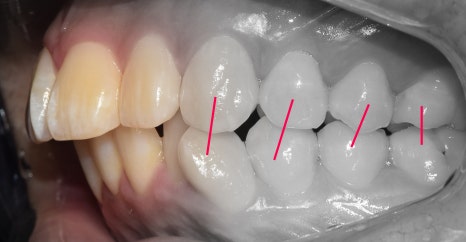

앞서, 1치대 1치 관계에 있던 교합관계들이

1치대 2치의 관계로 바뀐것을 볼 수 있으면서

길쭉하게 느껴졌던, U shape 형태의 악궁이

딱 보기 좋은, U shape 로 바뀌었죠.